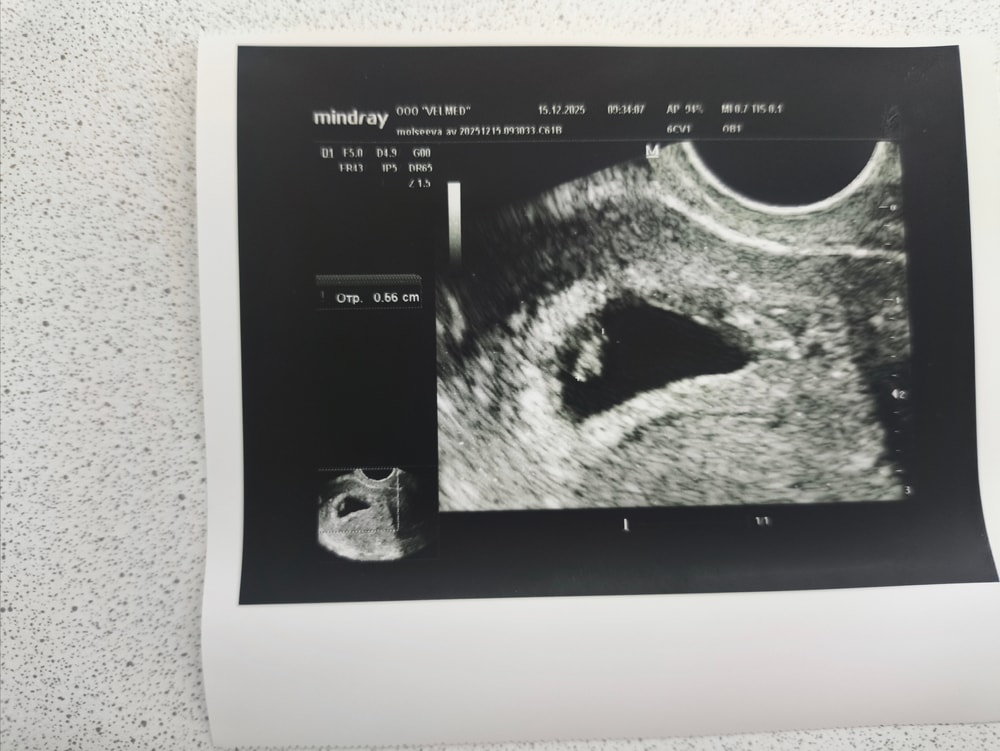

Девочки, посмотрите пожалуйста узи

жду ответа от ре, смущает форма пя, смотрели вагинальным датчиком